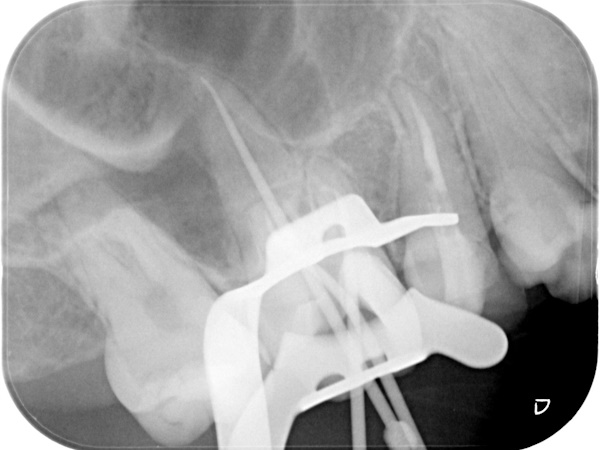

根管治療中(試適時)